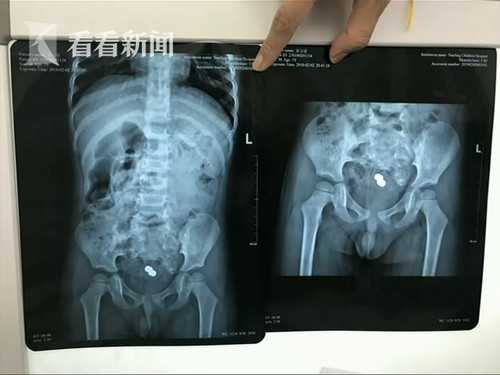

Hình ảnh chụp x-quang được bác sĩ cung cấp.

Bác sĩ nhi khoa tại bệnh viện Nam Y cho biết: "Vì đồ chơi này có góc cạnh nên đã chọc vào hậu môn của bé, khiến hậu môn bị tổn thương và bé cũng rất sợ hãi. Nghe nói ăn rau hẹ có thể giải quyết nhanh vấn đề này, họ đã ép con ăn rất nhiều khiến cho chất thải tích tụ không thể thoát ra ngoài được".

Dị vật mà bé Khang Khang nuốt phải là một món đồ chơi có góc cạnh.

Sau khi sử dụng biện pháp nội soi cùng 1 số dụng cụ chuyên nghiệp, bác sĩ đã gắp được 1 chú chó đồ chơi dài 2cm, rộng 1.5cm ra khỏi cơ thể bé trai. Bác sĩ nói thêm, nếu cứu chữa chậm trễ, ruột non của bé có thể bị hỏng vĩnh viễn.